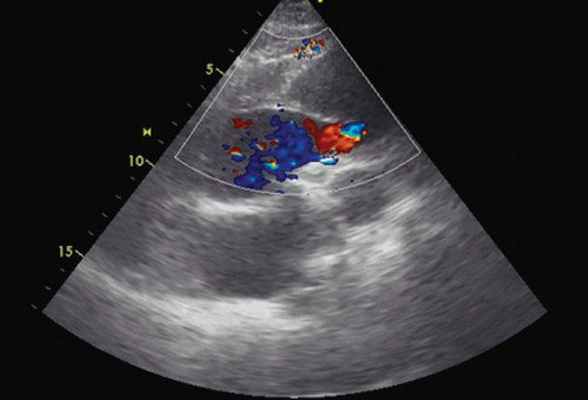

Рис. 3. Эхокардиограмма больного Ж. Режим ЦДК. Парастернальная позиция по длинной оси с фокусом на восходящий отдел аорты. Заполнение цветом просвета истинного канала аорты.

Помимо гипертрофии миокарда левого желудочка, склеротически измененных створок аортального клапана и наличия его недостаточности I степени, обращало на себя внимание расширение восходящего отдела аорты до 4,5-5,1 см (на различных уровнях) (рис. 1). Исследование средних отделов восходящей аорты (рис. 2) позволяло выявить нитевидную, невыраженно флотирующую структуру, расположенную по передней стенке аорты, формирующую истинный и ложный каналы аорты, которые более детально верифицировались в режиме ЦДК (рис. 3). В слепом участке ложного канала определялись тромботические массы. При исследовании из супрастернального доступа в области дистального отдела восходящей аорты и ее дуги лоцировался участок отслоения интимы (рис. 4). В остальных отделах аорты, доступных для визуализации, патологии выявлено не было. Таким образом, ультразвуковое исследование сердца позволило диагностировать расслаивающую аневризму восходящего отдела и дуги аорты (тип II по De Bakey). Проведенная МСКТ подтвердила данный диагноз (рис. 5).